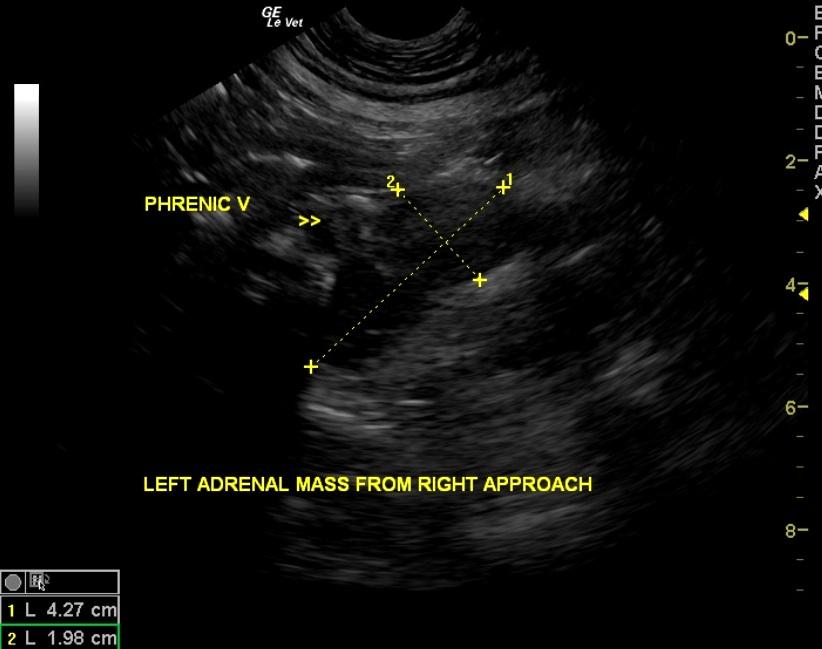

A 10-year-old FS Bull Mastiff dog with a history of urinary tract infections was presented for vomiting, polyuria/polydypsia, and pollakiuria. The urine appeared turbid, and analysis revealed isosthenuria, proteinuria, pyuria, and hematuria. Urine culture yielded E.coli. Abnormalities on CBC and serum biochemistry were monocytosis, mildly elevated ALP activity, and elevated lipase.